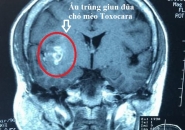

Triệu chứng giun sán chó mèo. Bệnh sán chó có thể gây mù lòa khi ấu trùng di chuyển đến mắt, gây liệt, u não, thậm chí tử vong nếu di chuyển đến não.

Dấu Hiệu Nhận Biết Sán Lên Não